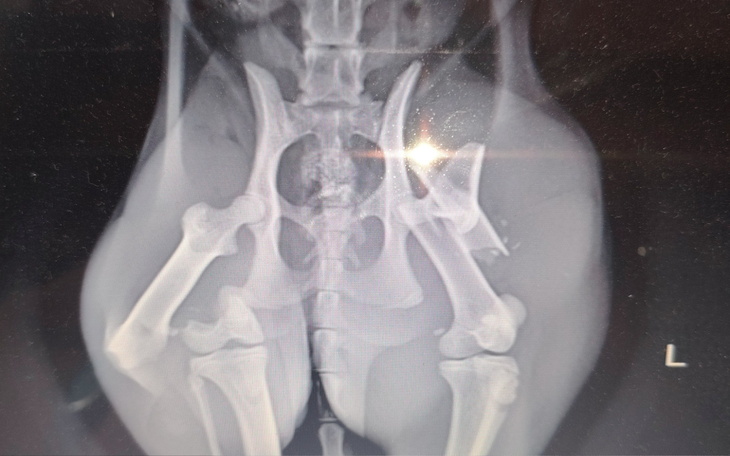

Potracona kotka znaleziona na poboczu. Zawieziona do weta. Okazało się 2 połamane łapki. Decyzja. Ratowanie kota. Koszt 2500 na chwilkę obecna. Operacja udana. Po tygodniu kotka zdjęła gips pod naszą nie obecność. Kość udowa na wieszchu. Natychmiastowa wizyta u weta. Decyzja lekarza amputacja. 07.07.2025 wizyta i rozmowa o ratowaniu łapki.